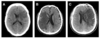

**IVH** - On CT imaging it appears as hyperdensity within the dark CSF spaces within the ventricles.

Left subdural with some midline shift

Subdural on CT head

Extradural on CT head

Subarachnoid haemorrhage on CT head